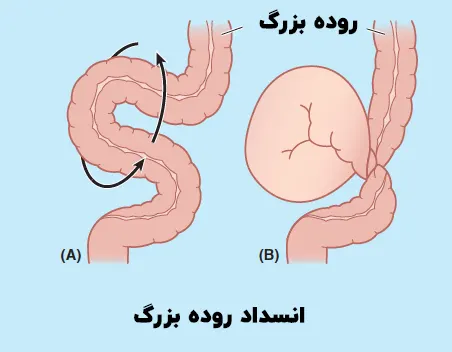

انسداد روده بزرگ یا کولون یک وضعیت پزشکی وخیم است که نیاز به مداخله سریع دارد. انسداد روده از عبور طبیعی غذا، مایعات و گازها جلوگیری می کند. انسداد می تواند در هر نقطه از دستگاه گوارش، از روده کوچک تا روده بزرگ (کولون) اتفاق بیفتد. چسبندگی، فتق، تومورها و بیماری التهابی روده (IBD) دلایل معمول انسداد روده هستند. انسداد روده بزرگ می تواند کامل یا جزئی باشد که بر این اساس علائم مختلفی ایجاد خواهد کرد. اگر متوجه علائم انسداد روده شدید فورا باید به دنبال مراقبت های پزشکی باشید. زیرا به جلوگیری از عوارضی مانند ایسکمی روده، سوراخ شدن و سپسیس کمک می کند. در واقع مداخله زود هنگام نه تنها علائم را تسکین می دهد بلکه خطر عوارض را نیز کاهش خواهد داد. انسداد روده به روش های مختلفی درمان می شود. با این حال، اگر اقدامات برای تسکین علائم کارساز نباشد، ممکن است نیاز به گذاشتن استنت یا جراحی برای برداشتن انسداد باشد.

انسداد روده بزرگ یک عارضه رایج است که دلایل مختلفی دارد و می تواند منجر به انسداد جزئی یا کامل روده شود. دلایل این بیماری به شرح زیر است:

- درهم روی روده: همانطور که از اسم آن پیداست درهم روی روده به وضعیتی گفته می شود که بخشی از روده به داخل بخش دیگر فرو رفته و باعث انسداد روده می شود.